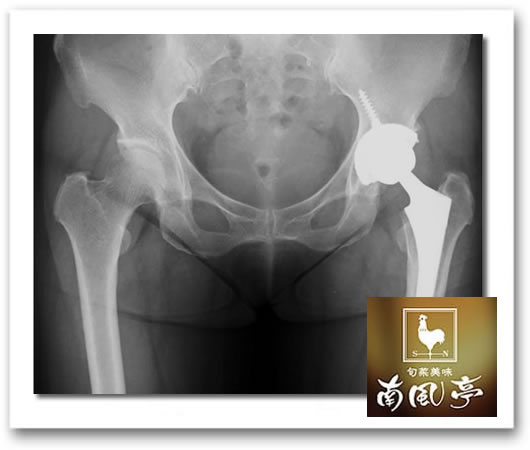

fumie 左股関節に人工関節を入れて3年過ぎました✨✨ 入れてすぐに2回ほどウッカリ脱臼をして救急搬送されましたがその後は超がつくほど元気になりました🤗 が、ここひと月、人工関節を入れたおみ足が骨盤あたりにかけて痛みがひどく、もう限界!なので病院へ。 人工関節が壊れたのかしら?ネットで調べたら内臓や骨に癌がある場合もそういう痛みが出ると書いてあったのでもしかしてそうなのかも…とちょっとブルーになりました。 レントゲンを指さしながら「炎症を起こしてます。筋肉疲労ですね。」と先生。 「ひゃー良かった!」と私ニッコリ😃 「えっ何が良かったの?何か重い物を持つとか過激な運動しました?」と聞かれて 「生樽を運ぶとか、食器をたんまりお盆に乗せて運ぶとか、そんなもんでしょうか?でも27年間ずっと続けてるんですよ。」と私。 「兎に角湿布して痛み止め飲んで安静にしてれば1ヶ月くらいで痛みは取れますから…❗️人工関節は異常ないです。次回は一年後にね!。」 良かったです。人工関節に不具合はなかったし、骨肉腫でもなかった。アスリートでもないのに筋肉疲労? 可笑しくてふふっ(* ´ ˘ ` *) でも痛みは相変わらずなんです。安静にしてないものね。だから決めました。 急がない。重い物は持たない。接待中はソローリソローリ‼️片付けは小分けにして運ぶようにする‼️ これで痛みがなくなりますように🤗✨✨ やっぱり歳なんだねえ。もう少し自分に優しくしないといけないなと反省はしています。 今日ももうすぐ終わり。また明日愛に溢れたいい日でありますように💕💕 皆さんにとってハッピーな一日でありますように💕💕 おやすみなさい🤗✨✨

葉羽 写真は参考画像です。本人ではありません。